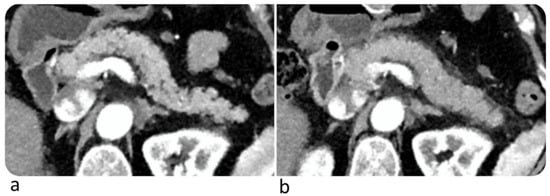

6.5. Pancreas